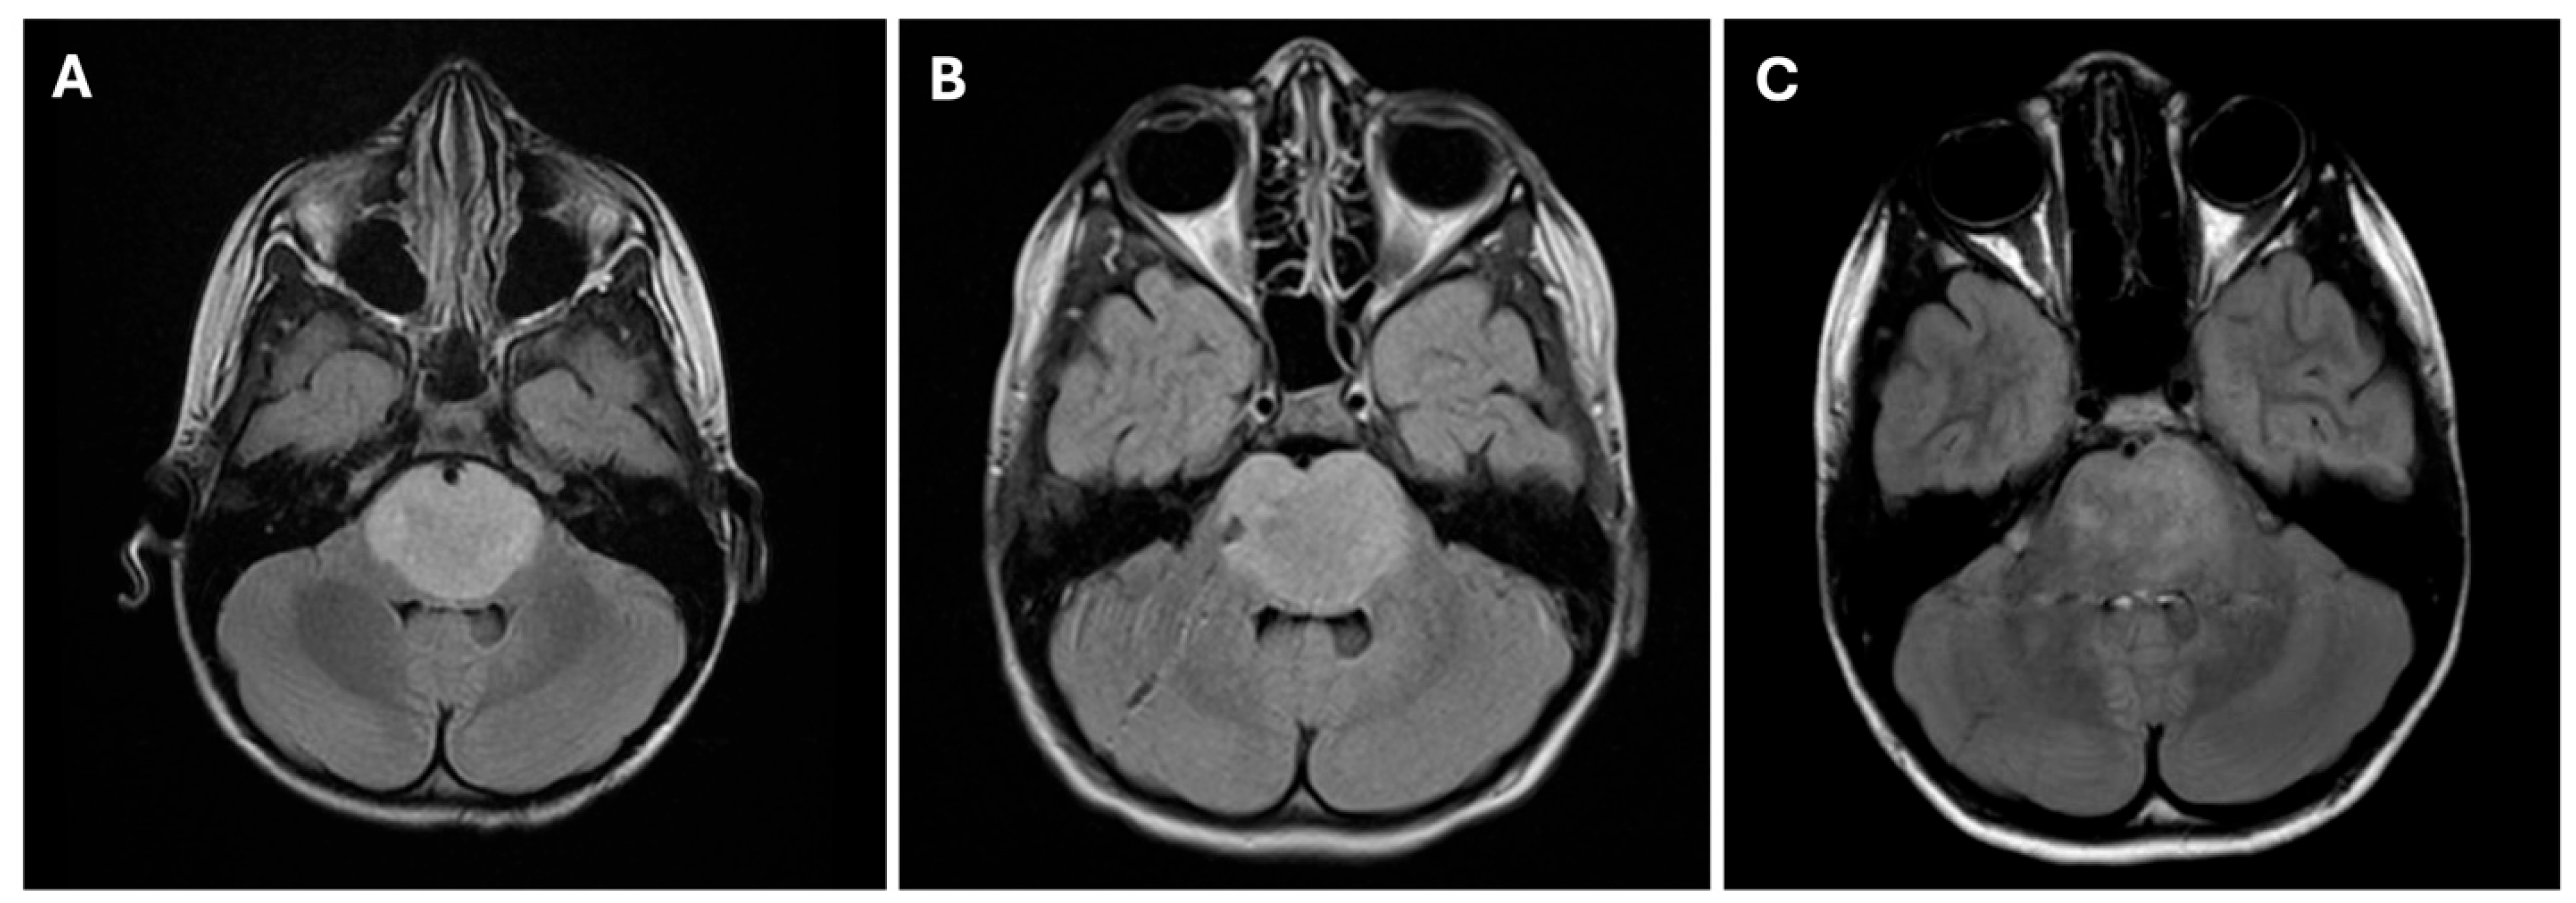

1. Introduction